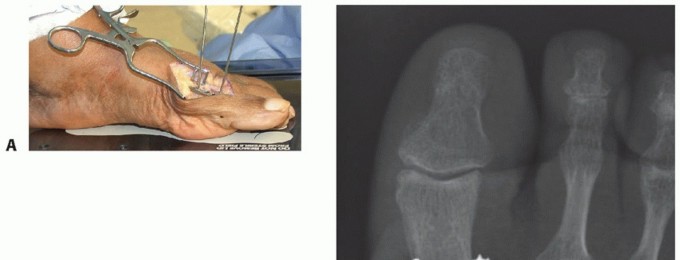

After preparing the joint surfaces, position the arthrodesis in 10 to 15 degrees of valgus, 10 degrees of dorsiflexion relative to the sole of the foot, and neutral pronation-supination.

Because it can be difficult to determine the plane of the sole with the patient on the operative table, a more predictable method of positioning the toe is to determine dorsiflexion relative to the first metatarsal axis. In most cases, the appropriate angle is about 25 to 30 degrees of dorsiflexion.3-5,12,17,19

The hallux is held provisionally with Kirschner wires or partially threaded guidewires from a cannulated screw set.

Confirm the positioning radiographically with a mini-fluoroscopy unit and clinically with use of a flat surface to simulate weight bearing (the cover of the screw set tray works nicely).12,16,23

The hallux should be slightly off the surface with the heel on the cover (TECH FIG 3A).9,23

Placing a finger or screwdriver handle under the heel simulates a shoe with a small heel; in this case, the pulp of the distal hallux should just barely engage the surface.

Cannulated or solid screws can be used per the surgeon's preference.23 We use 4.0- or 4.5-mm cannulated screws in most patients. Solid 3.5-mm cortical screws are an alternative (TECH FIG 3B).

Insert one guidewire from the medial aspect of the phalangeal base just distal to the metaphyseal flare and advance it across the arthrodesis site through the dorsolateral cortex of the metatarsal neck.

A second screw can be considered if the first screw provides insufficient fixation in patients with osteopenia. Place the second wire from the medial aspect of the metatarsal neck, just proximal to the flare of the medial eminence; advance this wire distally and slightly plantarly across the arthrodesis site to engage the plantar-lateral cortex of the phalanx.

- TECH FIG 3 • A. Positioning of the first MTP joint. A flat surface is used to position the toe properly. Note the positioning of the toe to allow for adequate clearance during gait. B. Postoperative radiograph shows the crossed-screw technique.